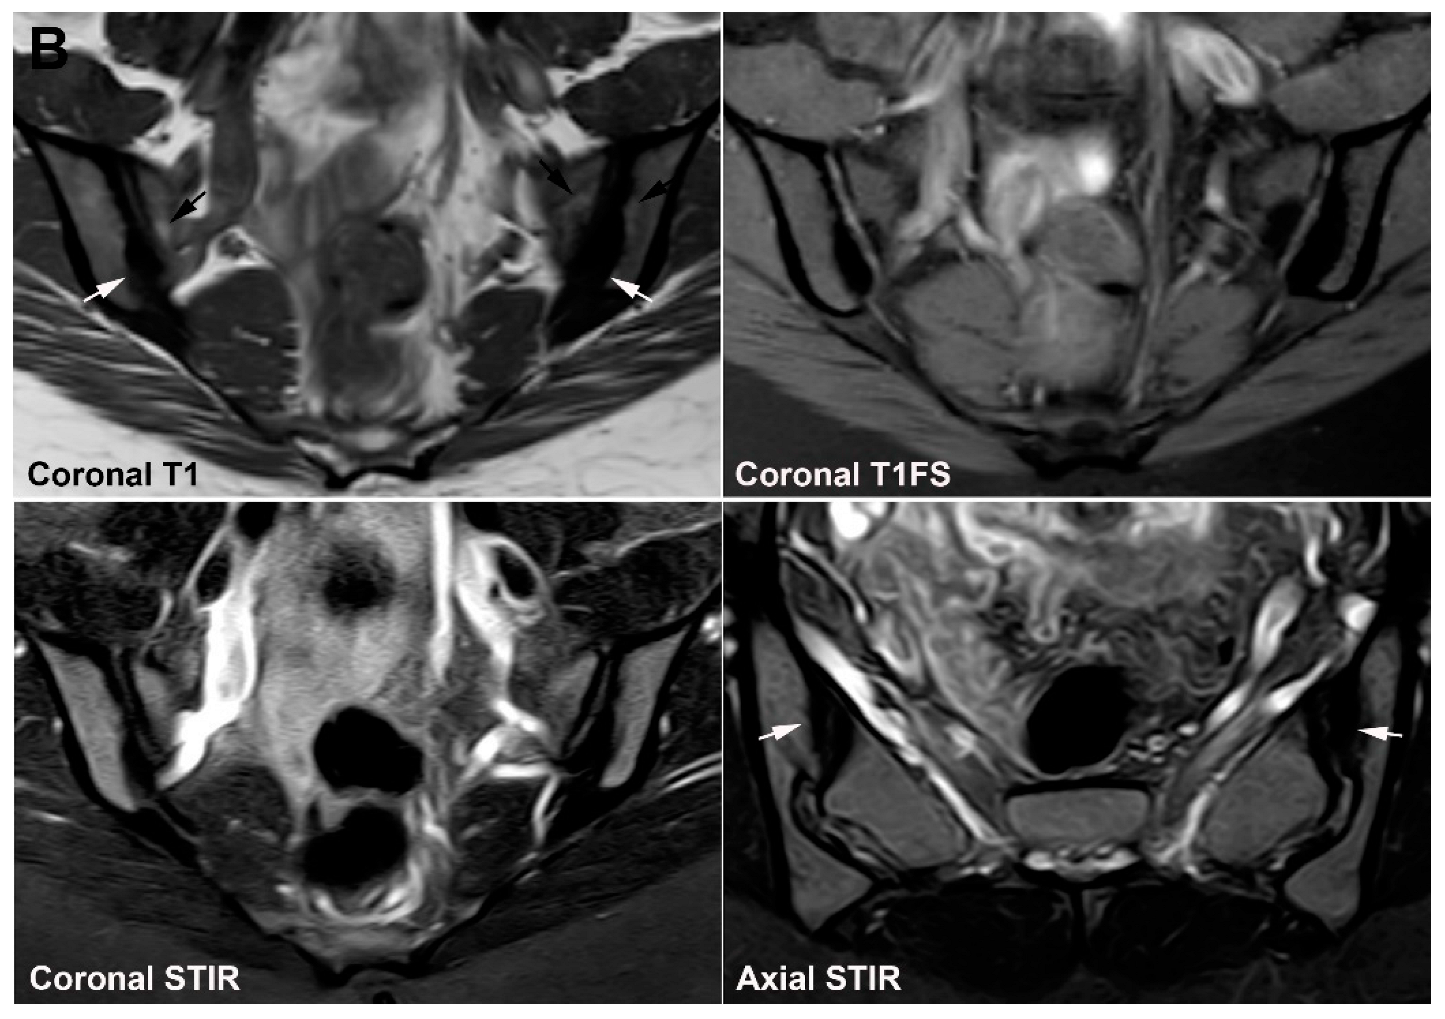

9. Infectious Sacroiliitis

10. Fractures

10.1. Sacral Stress Fracture

10.2. Sacral Insufficiency Fracture